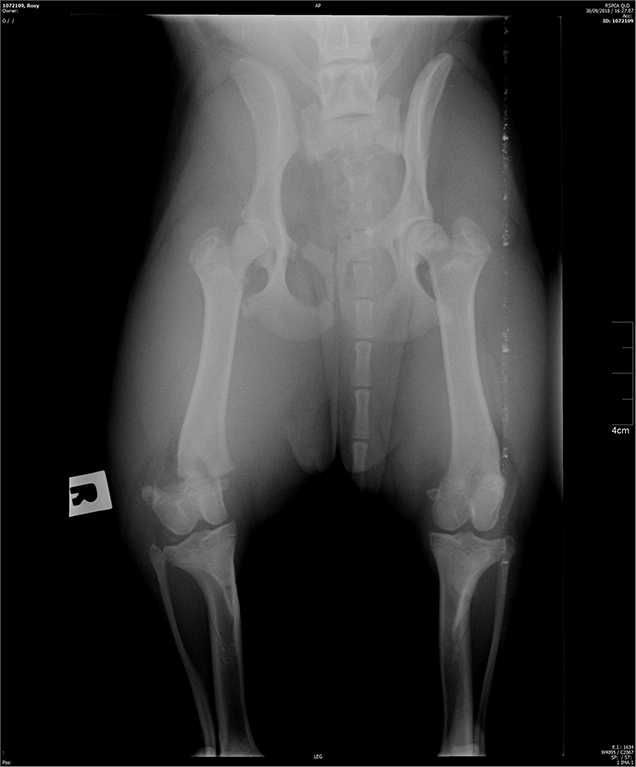

Roxy, a 7-month-old English Staffordshire Bull Terrier cross was surrendered to the RSPCA with a right hind distal femoral fracture. Her injury was sustained when she jumped out of the owner’s car window while in transit.